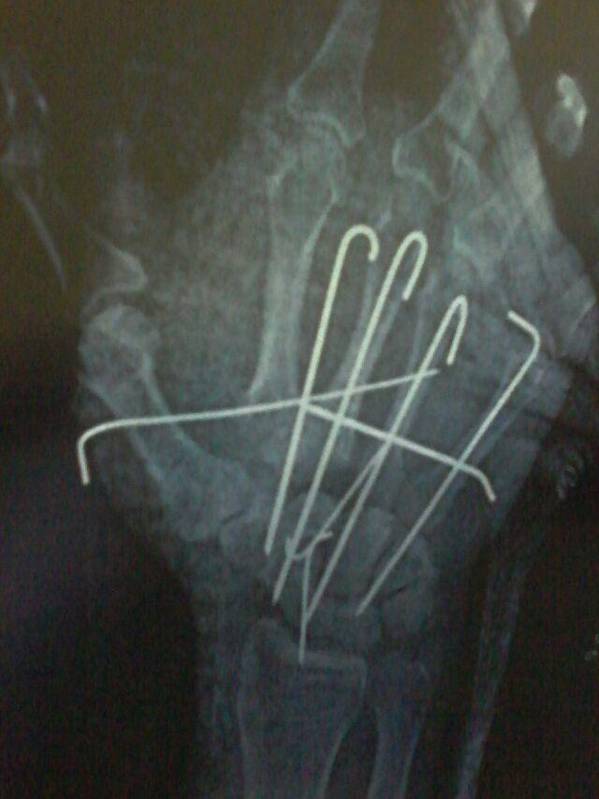

[修复重建] 右手绞榨伤

手被机器绞伤,伤后6小时入院,入院查环指无血运。术中发现桡侧腕长伸肌腱、示、中、环、小指伸肌腱腱性组织均从前臂内肌肉处撕脱,桡侧腕短伸肌腱止点撕脱,附着的腕骨脱出,第一、二、三腕掌关节不稳、脱位。望各位老师指教复位后正确固定的方法,后天复查X线后再上传。如果我固定错了就不发图了,还有肌腱怎样处理合理。如图:

今天复查术后X线结果,如有不对之处望各位老师指证

腕骨横向克氏针固定?